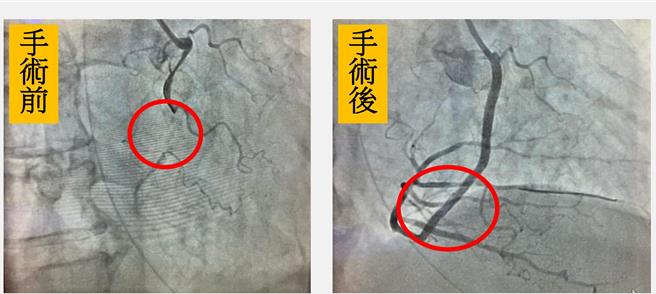

60岁林姓男子有心臟衰竭、慢性肾衰竭和糖尿病等多种慢性疾病,日前因新冠重症送急诊,发现右冠状动脉严重堵塞(左图),经皮冠状动脉治疗打通(右图),治疗3个礼拜终于好转出院。(大里仁爱医院提供/潘虹恩台中传真)

医疗团队经心导管检查发现林男右冠状动脉完全堵塞,左前降枝大约60至70%狭窄,为了避免显影剂引起之肾病变,先处理右冠状动脉,由血管内超音波发现瀰漫性钙化的病灶。王美英利用带刀片气球扩张术后及血管内超音波评估血管面积狭窄程度,并放置2支涂药支架,不但肺水肿改善,肾功能也没有恶化。